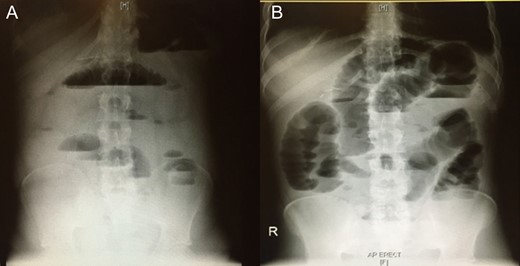

Blood was drawn for a complete blood count, urea and electrolytes, liver function test, coagulation profile, serum glucose level, carcinoembryonic antigen and cancer antigen, and the results were all within normal limits. An initial abdominal X-ray showed multiple air fluid levels and a dilated bowel (Fig. 1A and B). A computed tomography scan of the abdomen and pelvis showed small bowel obstruction to the level of the proximal ileal loops, with a transition point between the dilated proximal loops and the collapsed terminal ileal loops (Fig. 2A and B).

Initial abdominal x-ray showing multiple air–fluid levels (A) and a dilated bowel (B).